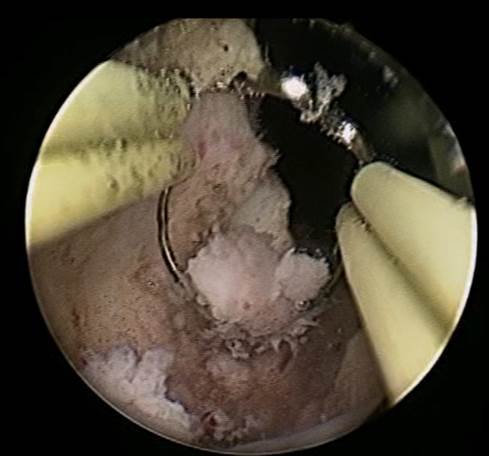

Se realiza uretrocistoscopía encontrando una tumoración en el tercio proximal de la uretra, de la cual se realizó una resección transuretral, encontrando que provenía del interior de un divertículo (Imágenes 2 y 3).